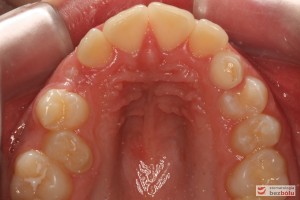

Rodzice zgłosili się z pacjentem celem rutynowej kontroli ortodontycznej. Wykonano OPG i po analizie modeli diagnostycznych stwierdzono brak miejsca dla wyrzynania dolnej prawej piątki stałej oraz zwężenie szczęki wraz z rotacją górnych zębów szóstych. W łuku górnym w pierwszym etapie leczenia zastosowano Rotator, celem odrotowania 6-tek stałych oraz ekspansji łuku w wymiarze poprzecznym. Następnie zamontowano aparat stały metalowy do uszeregowania zębów w łuku. W łuku dolnym miejsce odtwarzano stosując aparat stały i odpowiednią mechanikę leczenia. Leczenie aktywne trwało 3,5 roku, po czym zastosowano terapię retencyjną (retainer stały w żuchwie oraz Płytkę Hawley’a w szczęce).